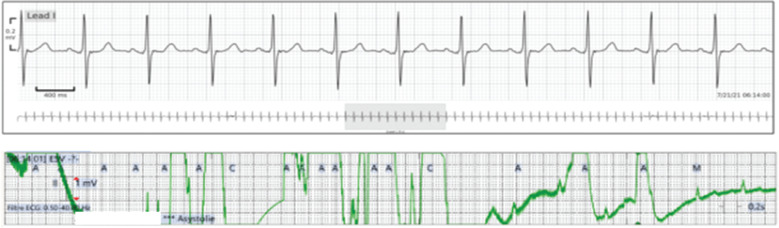

Figure 3:

Agreement between the two systems regarding the detection of a run of supraventricular tachycardia.